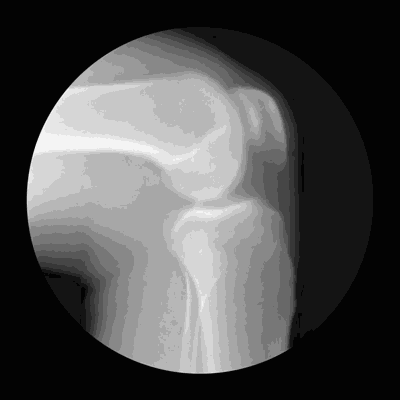

半月板是膝关节内的新月状(C型)纤维软骨结构 , 有缓冲作用 , 可以稳定膝关节 , 减轻膝关节负荷压力 。 膝盖疼痛、肿胀、发出响声等 , 是半月板损伤的典型症状 。